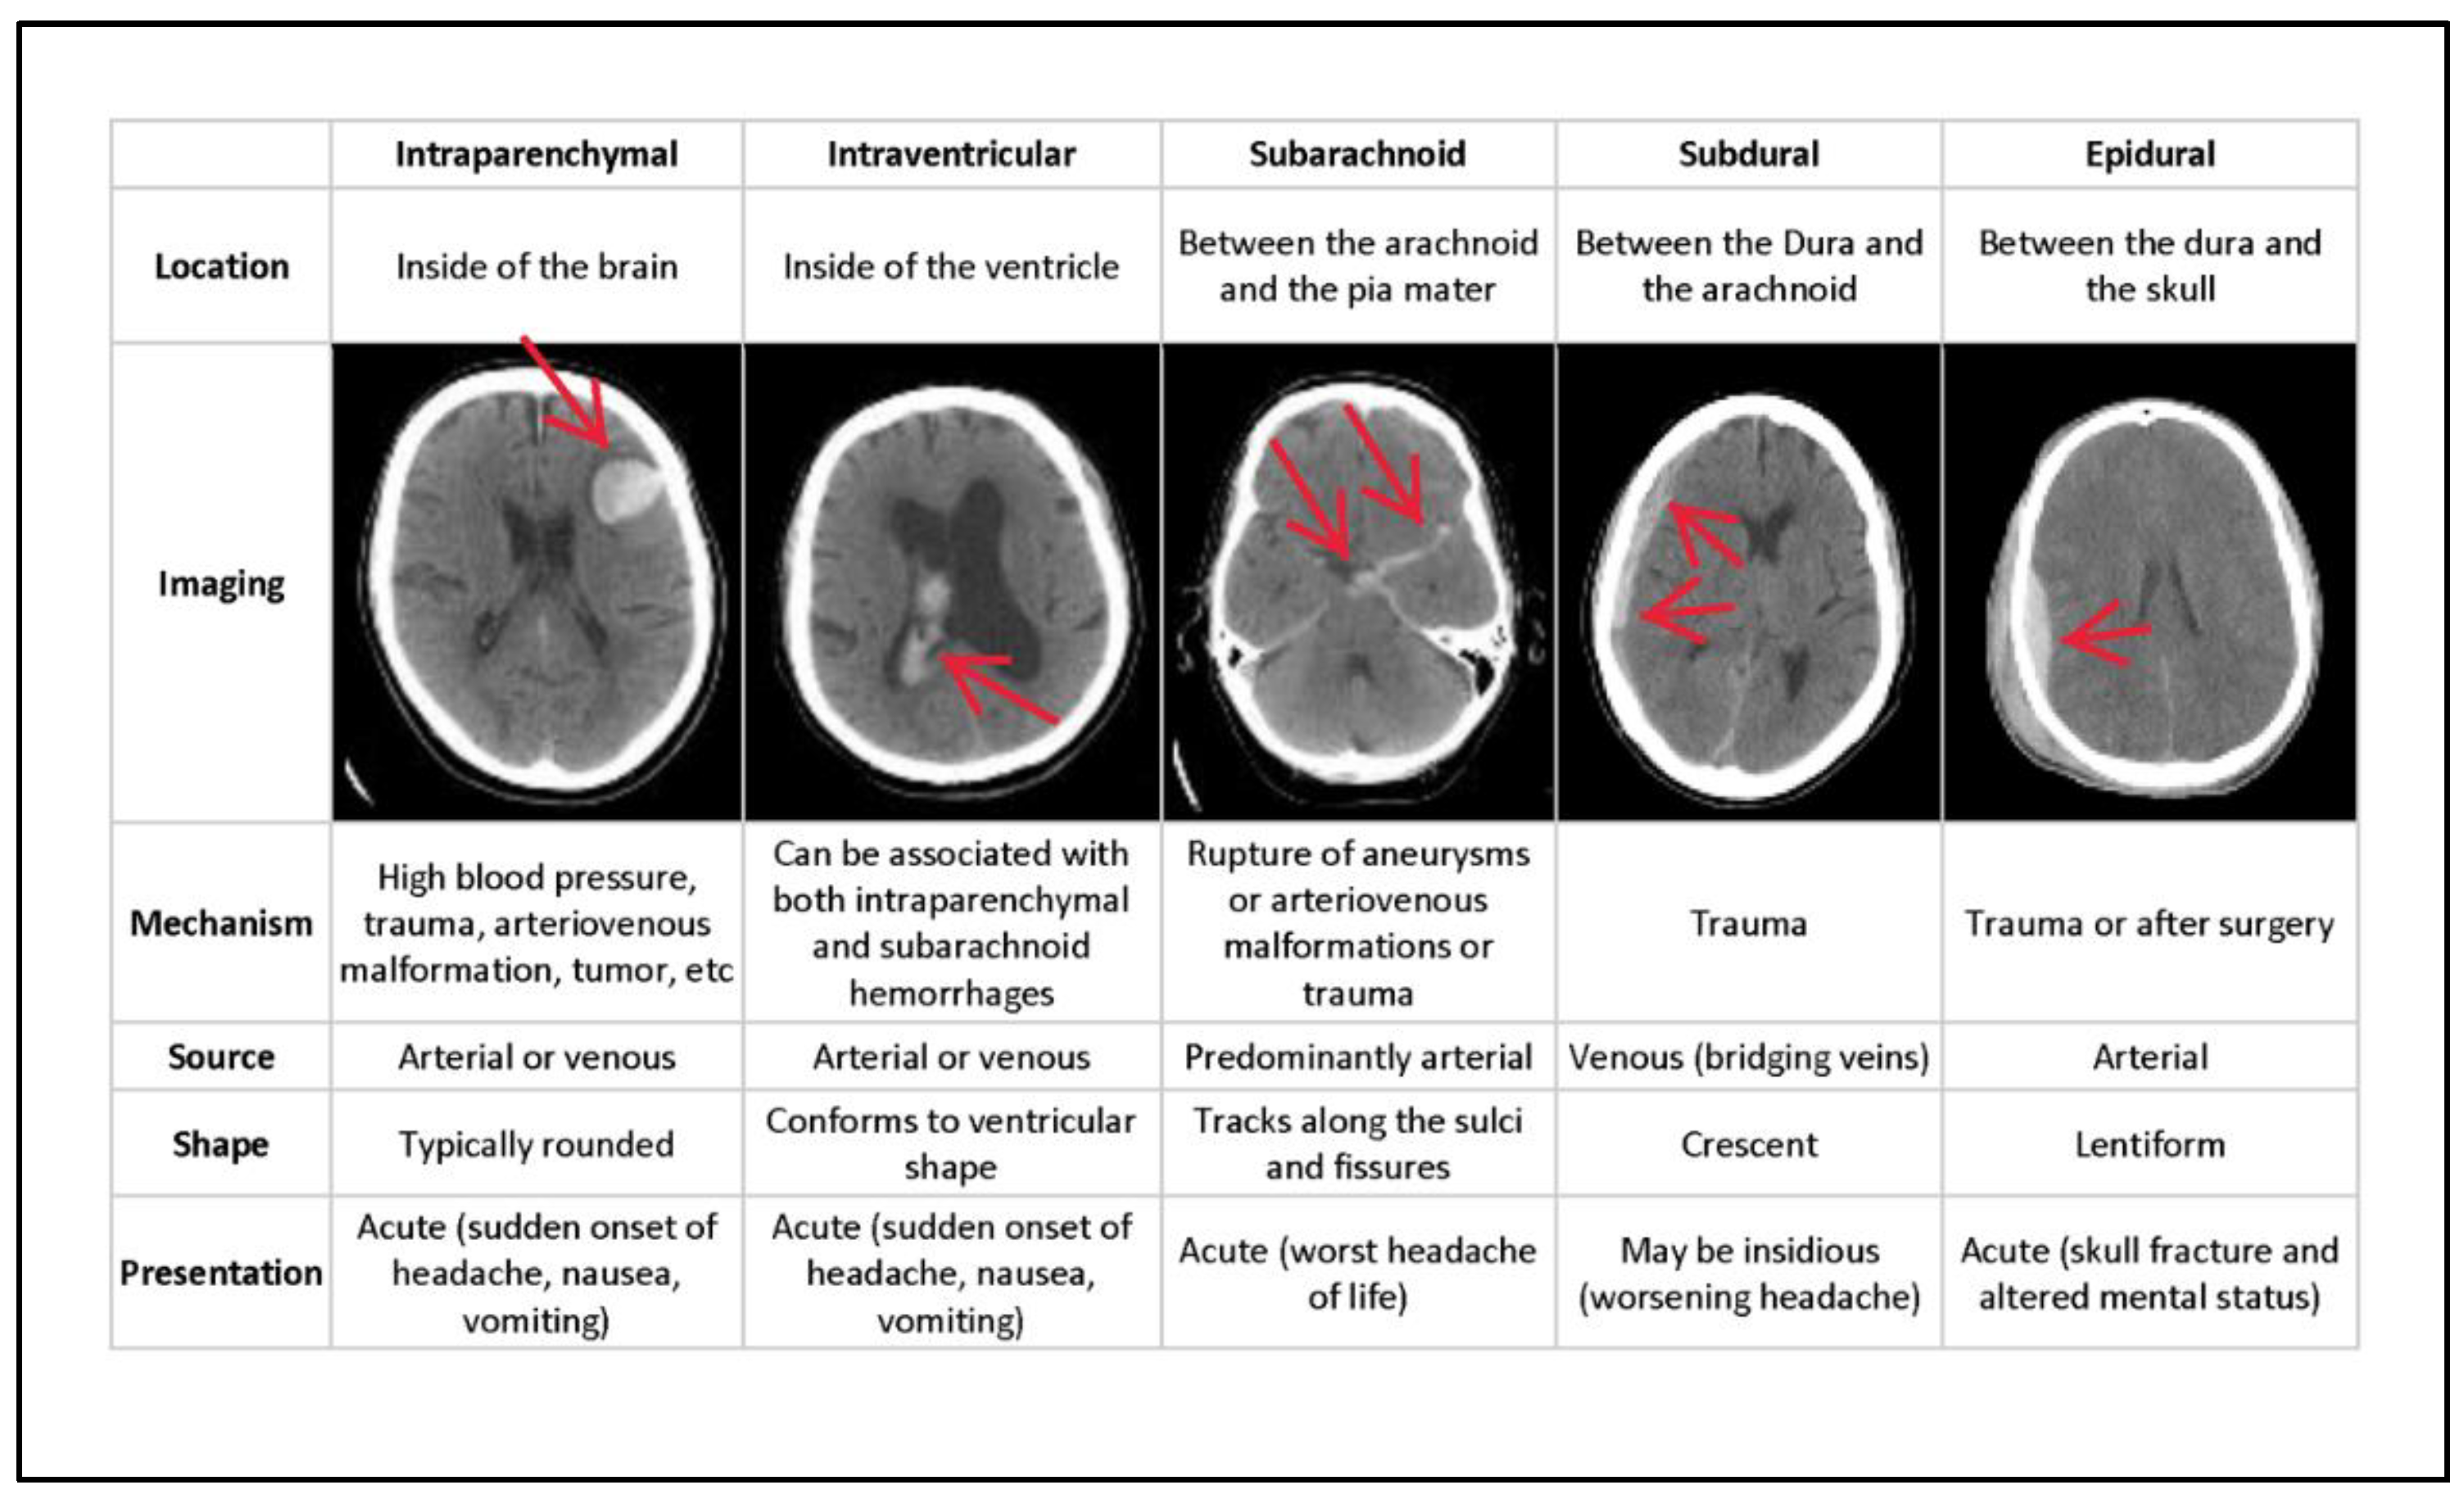

In general, ICH is divided into six categories of hemorrhages. Epidural (EPD) pain occurs as a result of an injury to the dura mater and skull. Intraparenchymal (ITP) happens when blood pools in brain tissues; intraventricular (ITV) occurs when bleeding enters the brain’s ventricular system. SBC arises when blood gathers beneath the arachnoid and the pia mater. Subdural (SBD) bleeding occurs when blood flows between the dura mater and the arachnoid mater, and some (SOME) bleeding is defined as any hemorrhage [8]. Figure 1 depicts the many forms of hemorrhages, with the sixth being classified as SOME or ANY hemorrhage. The different types of hemorrhage occur in different areas of the skull.

Figure 1.

Types of hemorrhages and their respective location inside the skull [9].

Figure 1 depicts the type of bleeding, as well as the location and specifics of the hemorrhage. Even though the output from the neural network does not provide any location information, this is used to pinpoint the bleeding. Epidural (EPD), Intraparenchymal (ITP), Intraventricular (ITV), Subarachnoid (SBC), Subdural (SBD), and more designations are conceivable (SOME). If there is some hemorrhage, the final label will be correct. Multiple hemorrhages can occur at the same moment in some real-life settings [10].